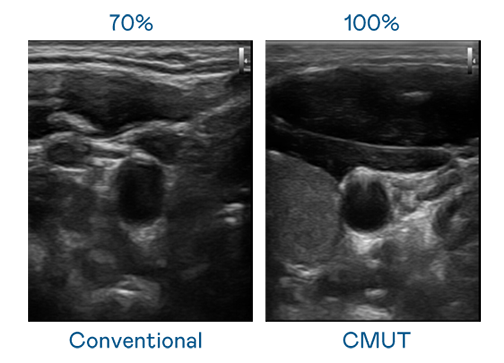

CMUT 技术是一种用电容式微机电元件来产生超音波讯号的技术。与传统 PZT 压电式技术相比,CMUT 频宽增加 30%,更宽频的超音波讯号让影像解析度大幅提升,是实现高影像品质医疗超音波扫描、促进精准医疗发展的关键技术。

大频宽带来超清晰影像

超音波影像的解析度高低,首先取决于探头能发出的讯号频宽。九游会·J9 CMUT 可提供高清晰的超音波讯号,提供高频宽、高灵敏度、影像纹理细节更高的超音波影像,协助医护人员缩短影像判读时间及利用精准的医疗影像进行诊断。